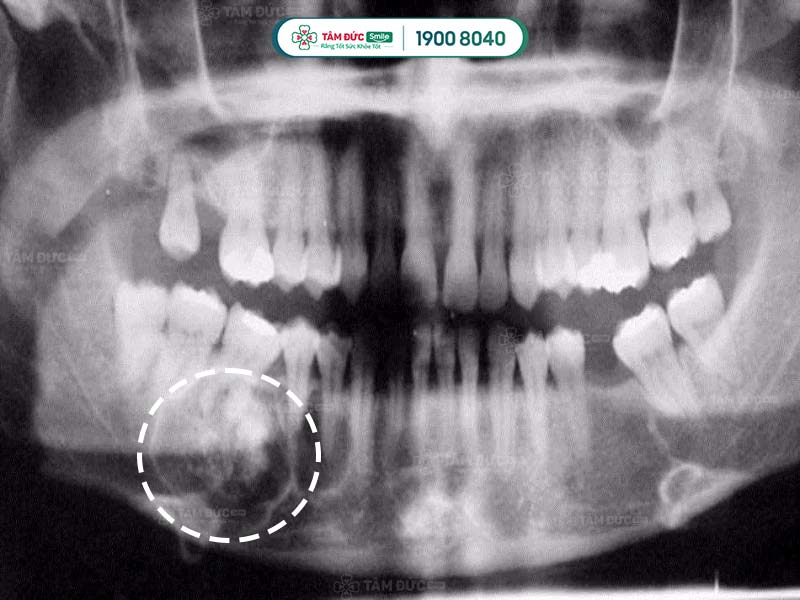

U răng qua phim chụp X-Quang

5.2. Chụp CT scan cho u răng

Sử dụng phương pháp chụp CT Scan để nhìn thấy rõ được cấu trúc bên trong khối u răng đó như thế nào.

Trong một số trường hợp cần thiết như u răng phức hợp phát triển vào khoang mũi. Cần thực hiện thêm 1 số xét nghiệm khác như chụp cộng hưởng từ MRI… Để có thể đưa ra được phương pháp điều trị phù hợp.